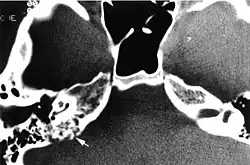

Imaging studies help to identify the tumor and the specific anatomic site of involvement. Magnetic resonance images show a hyperintensity (hypervascularity) of a heterogeneous mass by T1 weighted images. Computed tomography shows a multilocular, lytic destructive temporal bone mass, centered on the vestibular aqueduct (between internal auditory canal and sigmoid sinus).[1][6][7]